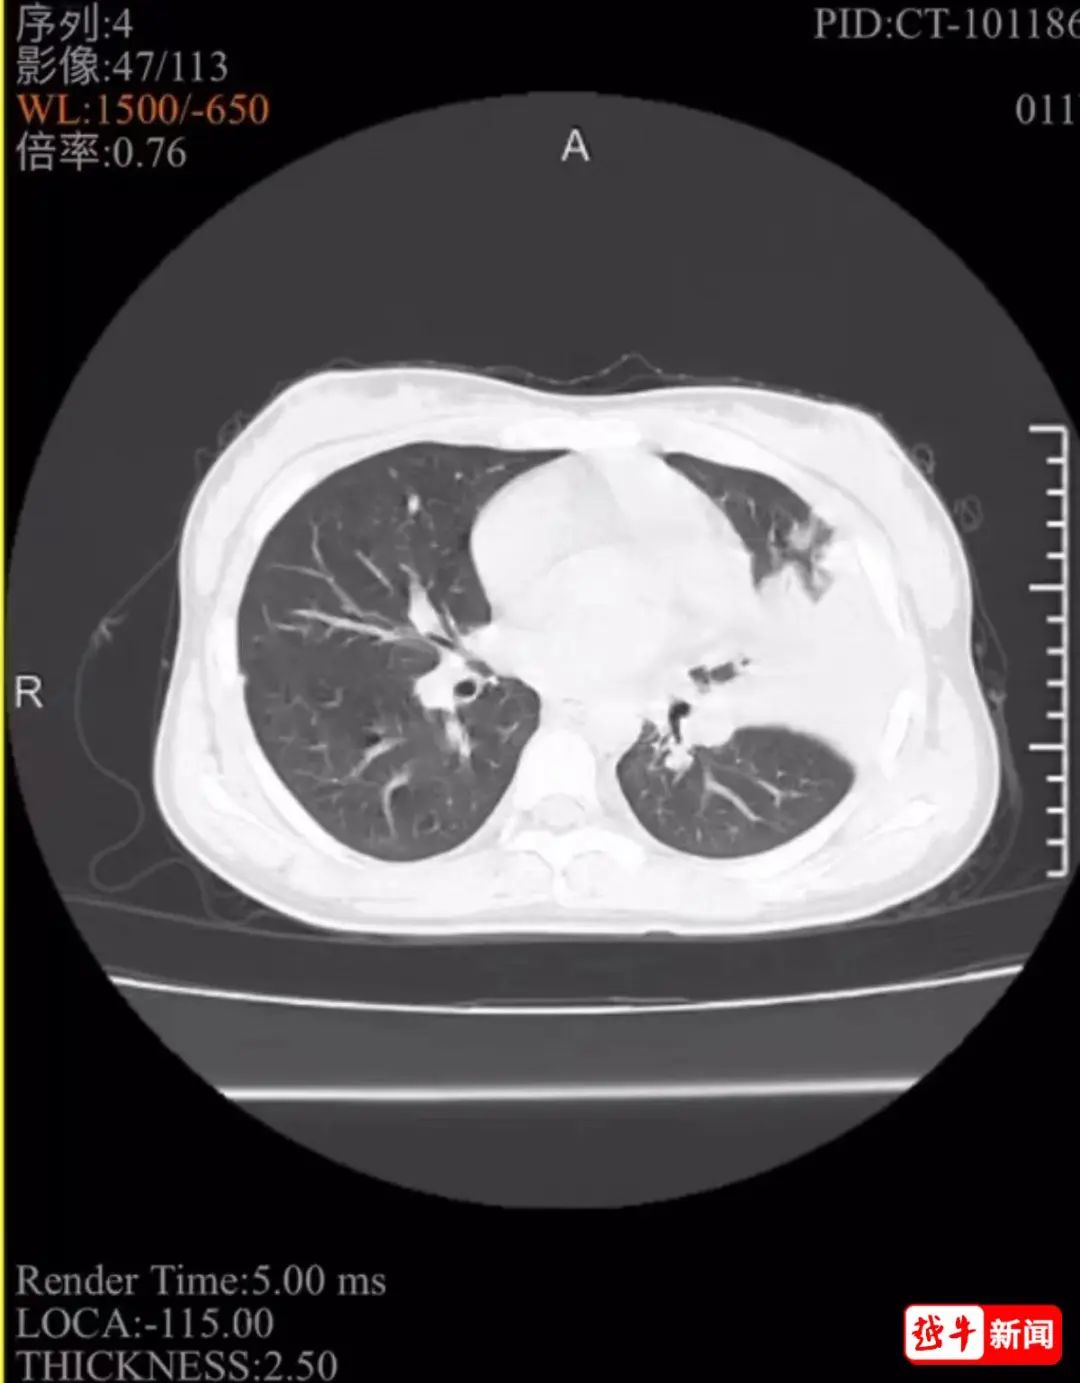

“發(fā)熱好多天了,最高飆到40℃”“吃了退燒藥管點用,但藥效一過,又燒起來”……最近你的孩子,出現(xiàn)了類似情況了嗎?今年11歲的紹興女孩敏敏(化名),發(fā)燒、咳嗽一周不見好轉(zhuǎn),體溫最高燒到39℃,家長將她送